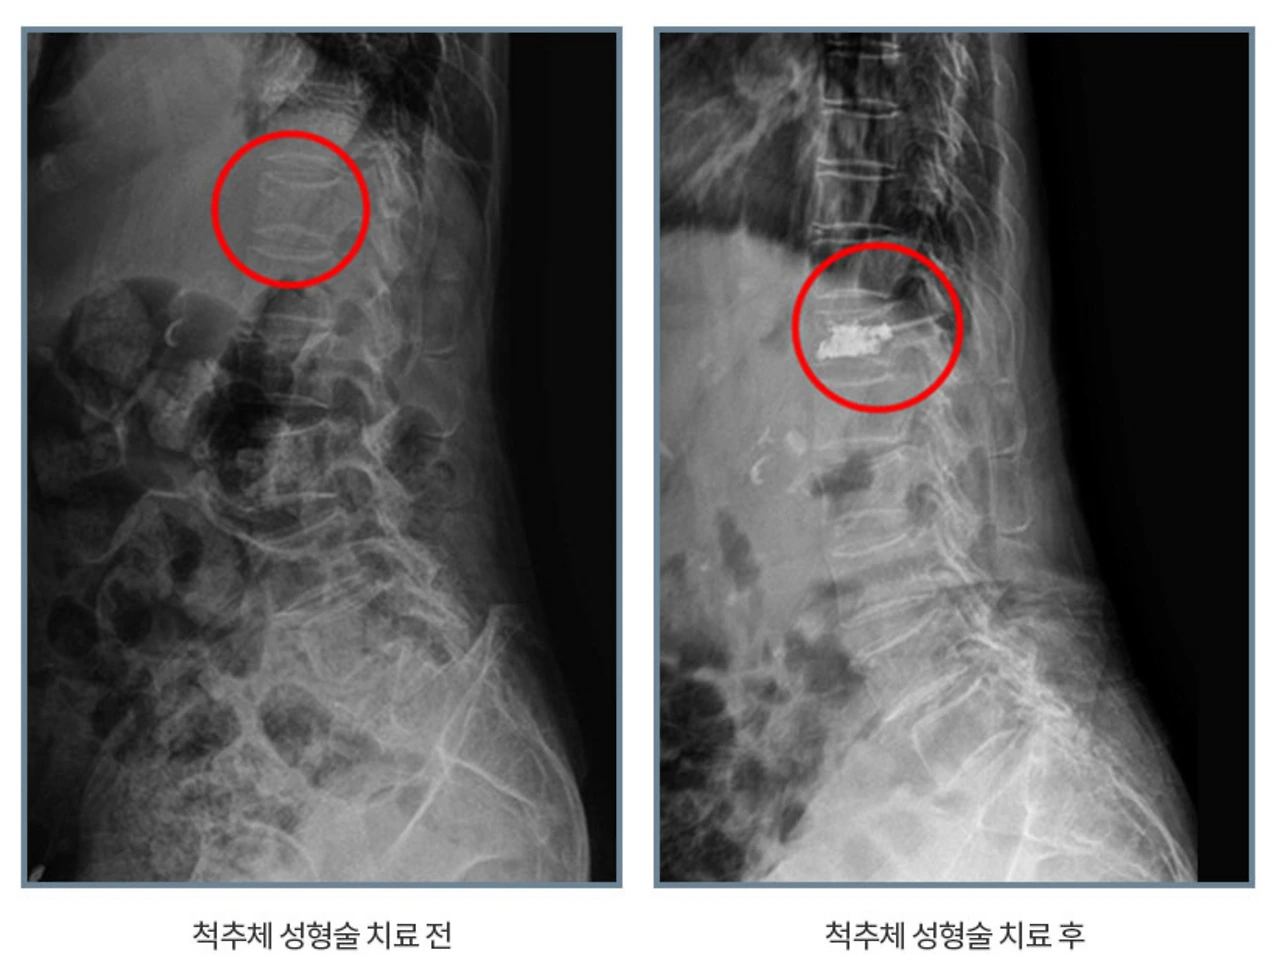

척추체성형술.PNG

전 의료진이 허리 스포츠 메이져 대학병원 전임의 출신인 에이스병원에서는 비수술적치료로 경피적 척추체성형술을 시행하는데요. 골절된 척추체에 주삿바늘로 골시멘트를 주입해 무너진 척추뼈를 바로 만드는 것이지요.

피부 국소마취만 시행한 후에 X-선 투시기를 보면서 골절된 척추체에 숙련된 전문의가 직접 골시멘트를 주입하는 척추체성형술은 골절로 인해 척추뼈가 심하게 주저앉거나 통증이 나아지지 않는 경우에 척추뼈의 높이를 회복시키는 방법으로 시행되고 있습니다.